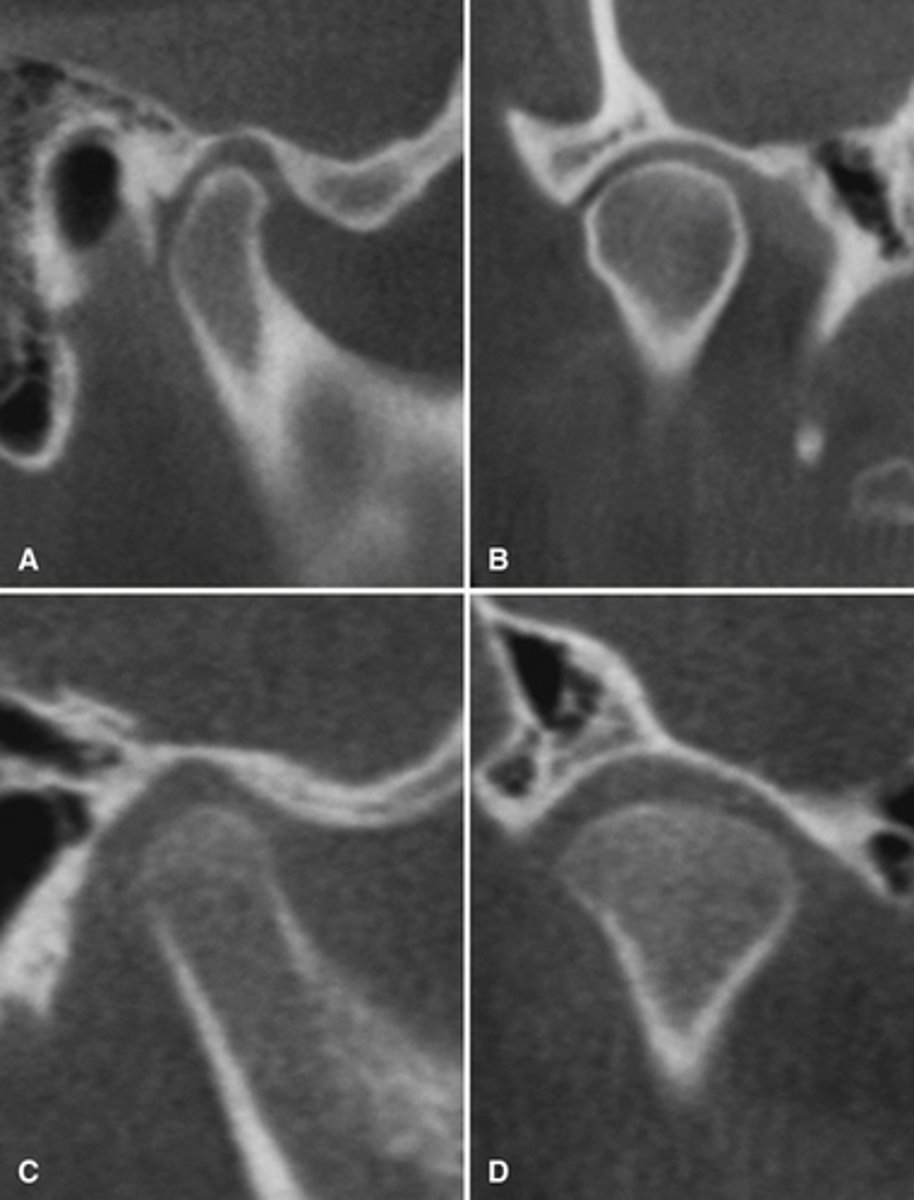

The bottom radiographs depict a developing 7year-old child.

1. The cortication of all the articulating surfaces are thin.

2. The mandibular fossa is shallow

3. The articular eminence is short

The top images are being compared to the bottom images, which patient is younger and what are all the ways to know this.